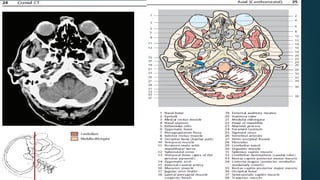

Este documento es el programa para un taller de imágenes del curso de emergencia 2015 impartido por el Dr. Víctor Delgado. El taller se centra en el uso de imágenes médicas para el diagnóstico y tratamiento de pacientes en coma traumático según la base de datos de Marshall. El Dr. Delgado es el único instructor repetido a lo largo del documento.